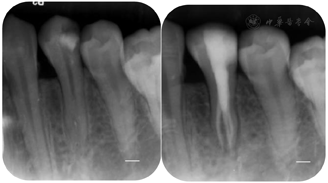

治疗过程:34去除暂封材料及棉球,洞壁见大量腐质,颊侧及舌侧的髓室顶未完全揭除(见图7A);去净腐质,玻璃离子制作假壁,上橡皮障,揭净髓室顶,显微镜下见髓腔狭窄,髓室底深。依据术前CBCT测量数据:髓室底距颊尖:14.0mm,髓室底距釉质牙本质界CEJ:6.5mm,在显微镜下,使用超声ET20去除牙本质领,修整、扩大髓室壁,建立直线通路。见髓室底有钙化物,同时去除髓室底钙化物,充分暴露髓室底,DG16仅探及颊侧通路,C+疏通,扩大至15#。在CBCT上对远舌通路进行定位,远舌通路位于颊侧通路远中舌侧约2.0mm(见图3F),显微镜下,ET25逐层去除根管口牙本质领,充分暴露远舌通路根管口,根管弯曲细小,伴有弥漫性钙化,依次使用6#、8#、10# C锉,尖端2mm预弯,结合EDTA凝胶逐号疏通根管,1%NaClO大量冲洗,回挫,电测根管长度:B=21.0mm,DL=19.0mm,镍钛预备根管,B:25# 6%,DL:25# 4%。试主尖,根尖片发现根管有遗漏(见图2B)。再次结合CBCT对近舌通路进行定位CBCT颊舌观:近舌牙根弯曲,根管影像不清(见图6B);横断面:近舌通路根管口位于颊侧通路远中舌侧1.5mm,远舌通路近中颊侧约1.0mm,近舌通路根管口牙本质领较厚(见图6A),显微镜下,ET25少量缓慢逐层去除1~2mm钙化物及牙本质领,小号锉反复探查,探及近舌通路根管口;疏通方法同远舌通路,电测根管长度:ML=19.0mm,EDDY尖结合1%NaClO声波活化荡洗,试主尖,X线片示:到达工作长度(见图2C),根管内封入Ca (OH )2糊剂,玻璃离子暂封。2周后复诊,患牙未诉不适,iRoot sp单尖充填3通路,髓腔热牙胶回填,完成根管治疗。术后拍摄X线片显示,根管充填恰填(见图2D)。

术后3月复诊,34无特殊不适,并完善冠部永久修复。